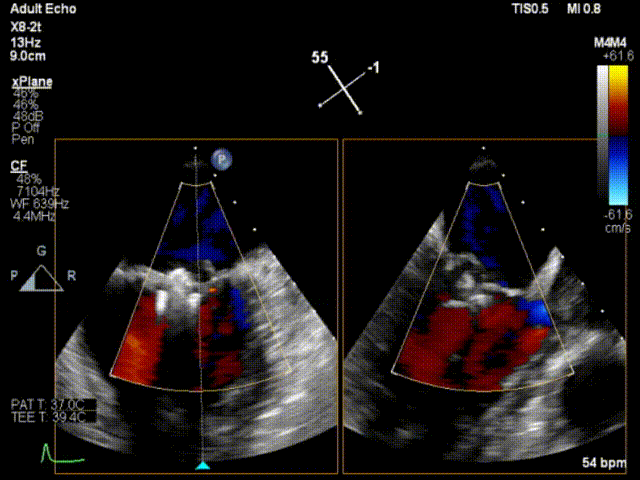

患者男性,63岁,主诉间歇性心悸5年,加重3月。门诊以“二尖瓣关闭不全”收入西京医院。术前超声提示:二尖瓣关闭不全,前叶26mm,后叶22mm,二尖瓣腱索断裂,后叶P1区及部分P2区脱垂,脱垂高度9mm,脱垂宽度15mm,舒张期瓣口面积约6.8cm²,反流束位置位于1区偏2区,Carpentier分型Ⅱ型,心功能Ⅳ级(NYHA分级)。

术前超声心动图1